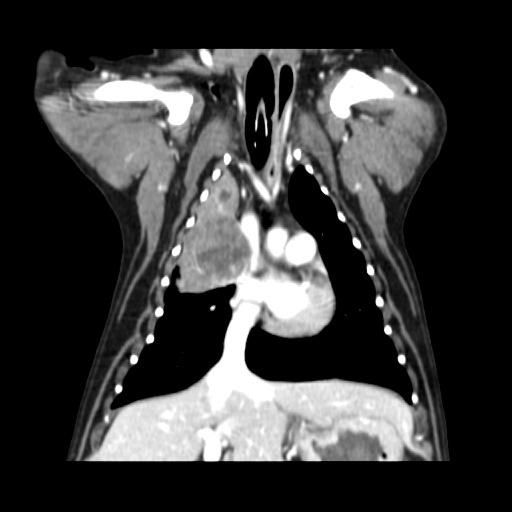

강아지 폐 종양 기수(진행 현황)에 대해 궁금합니다

엑스레이와 CT를 보았을 때, 강아지 폐암이 몇 달 정도 진행된건지 알 수 있을까요?

약 2~3주간 기침, 가래 증상만 있던 상태입니다.

폐종양은 보통 아무증상없이 수개월~수년에 걸쳐 발생하는게 일반적이나 드문경우 수주에 걸쳐 하게 커지기 때문에 영상검사 결과만으로 발생 기간을 추정할 수 없습니다.